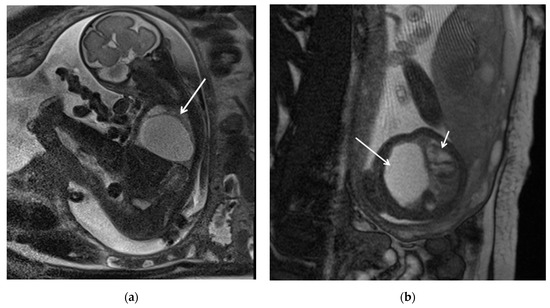

In prenatal diagnosis, MRI is valuable for better delineating and locating the mass. It also helps in assessing the contralateral lung. Key diagnostic signs on MRI include higher signal intensity than normal lung tissue, lower signal intensity than amniotic fluid, and the visible supply artery arising from the aorta (Figure 7) [8,11].

Figure 7. BPS at 27 weeks gestation. The coronal image shows a mass with higher signal intensity than the normal lung but lower signal intensity than amniotic fluid. The consolidation shifts the heart to the right (black arrow). There is a feeding artery from the aorta to suggest the diagnosis of sequestration (blue arrow).